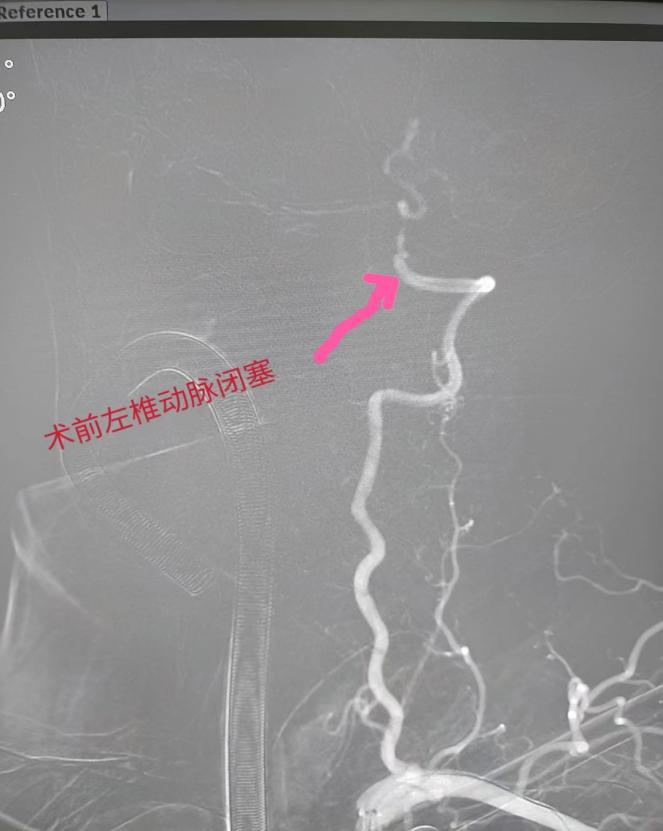

在导管室行全脑血管造影检查,明确为椎动脉闭塞后靠脊髓前动脉部分代偿基底动脉。神经内科团队立即给患者行椎基底动脉介入取栓和支架植入手术,成功开通血管,饶大叔安返病房,目前其说话清晰,肌力基本恢复正常,日常生活能自理。